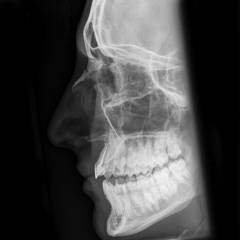

| Рентгенография черепа | На снимках видны линии перелома, количество и смещение отломков. Исследование позволяет выявить не только перелом носовых костей, но и повреждения черепа. | Исследование не требует специальной подготовки и занимает около 2 минут. Снимки делают в двух проекциях – анфас и профиль. |

| Рентгенография черепа | Рентгеновские снимки показывают линии переломов, количество фрагментов и их смещение. Исследование выявляет переломы носовых костей и повреждения черепа. | Подготовка не требуется, исследование занимает около 2 минут. Снимки делают в двух проекциях: анфас и профиль. В некоторых случаях могут потребоваться другие проекции. |